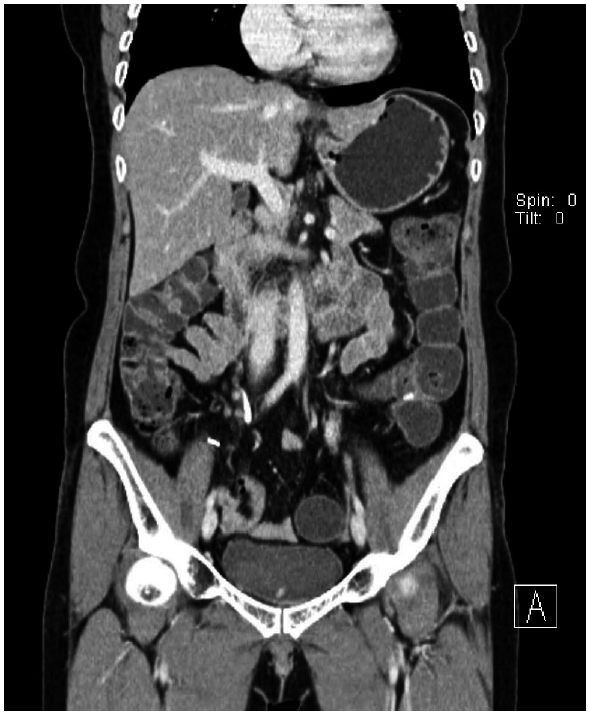

She was transferred to our hospital on 10 November 2011. At that time, physical examination revealed tenderness in the left lower quadrant of the abdomen. A blood test showed eosinophilia. WBC count was 8,200/μl, and the proportion of eosinophils was 13.8%. CRP was 7.41 mg/dl, and serum electrolytes and liver enzymes were within normal range. An abdominal CT showed 3 abscesses in the left upper quadrant, mesentery, and pelvic cavity. On the 11th hospital day after transfer (21 November 2011), a 4th abdominal CT was performed. Two abscesses were found in the anterior aspect of the distal transverse colon (4 cm) and the interbowel space of the left mid abdomen (3.5 cm) (Fig. 1A, B). The abscess in the pelvic cavity had disappeared. Small bowel series and colonoscopy showed no remarkable findings except a diverticulum at the duodenal third portion.

Fig. 1.

(A) Abdominal CT showing 2 abscesses in the anterior aspect of the distal transverse colon (4 cm, arrow) in the interbowel space of the left middle abdomen (3.5 cm). (B) The coronal view of (A). The arrow indicates the abscess of the interbowel space of the left middle abdomen.

Fig. 1. (A) Abdominal CT showing 2 abscesses in the anterior aspect of the distal transverse colon (4 cm, arrow) in the interbowel space of the left middle abdomen (3.5 cm). (B) The coronal view of (A). The arrow indicates the abscess of the interbowel space of the left middle abdomen.